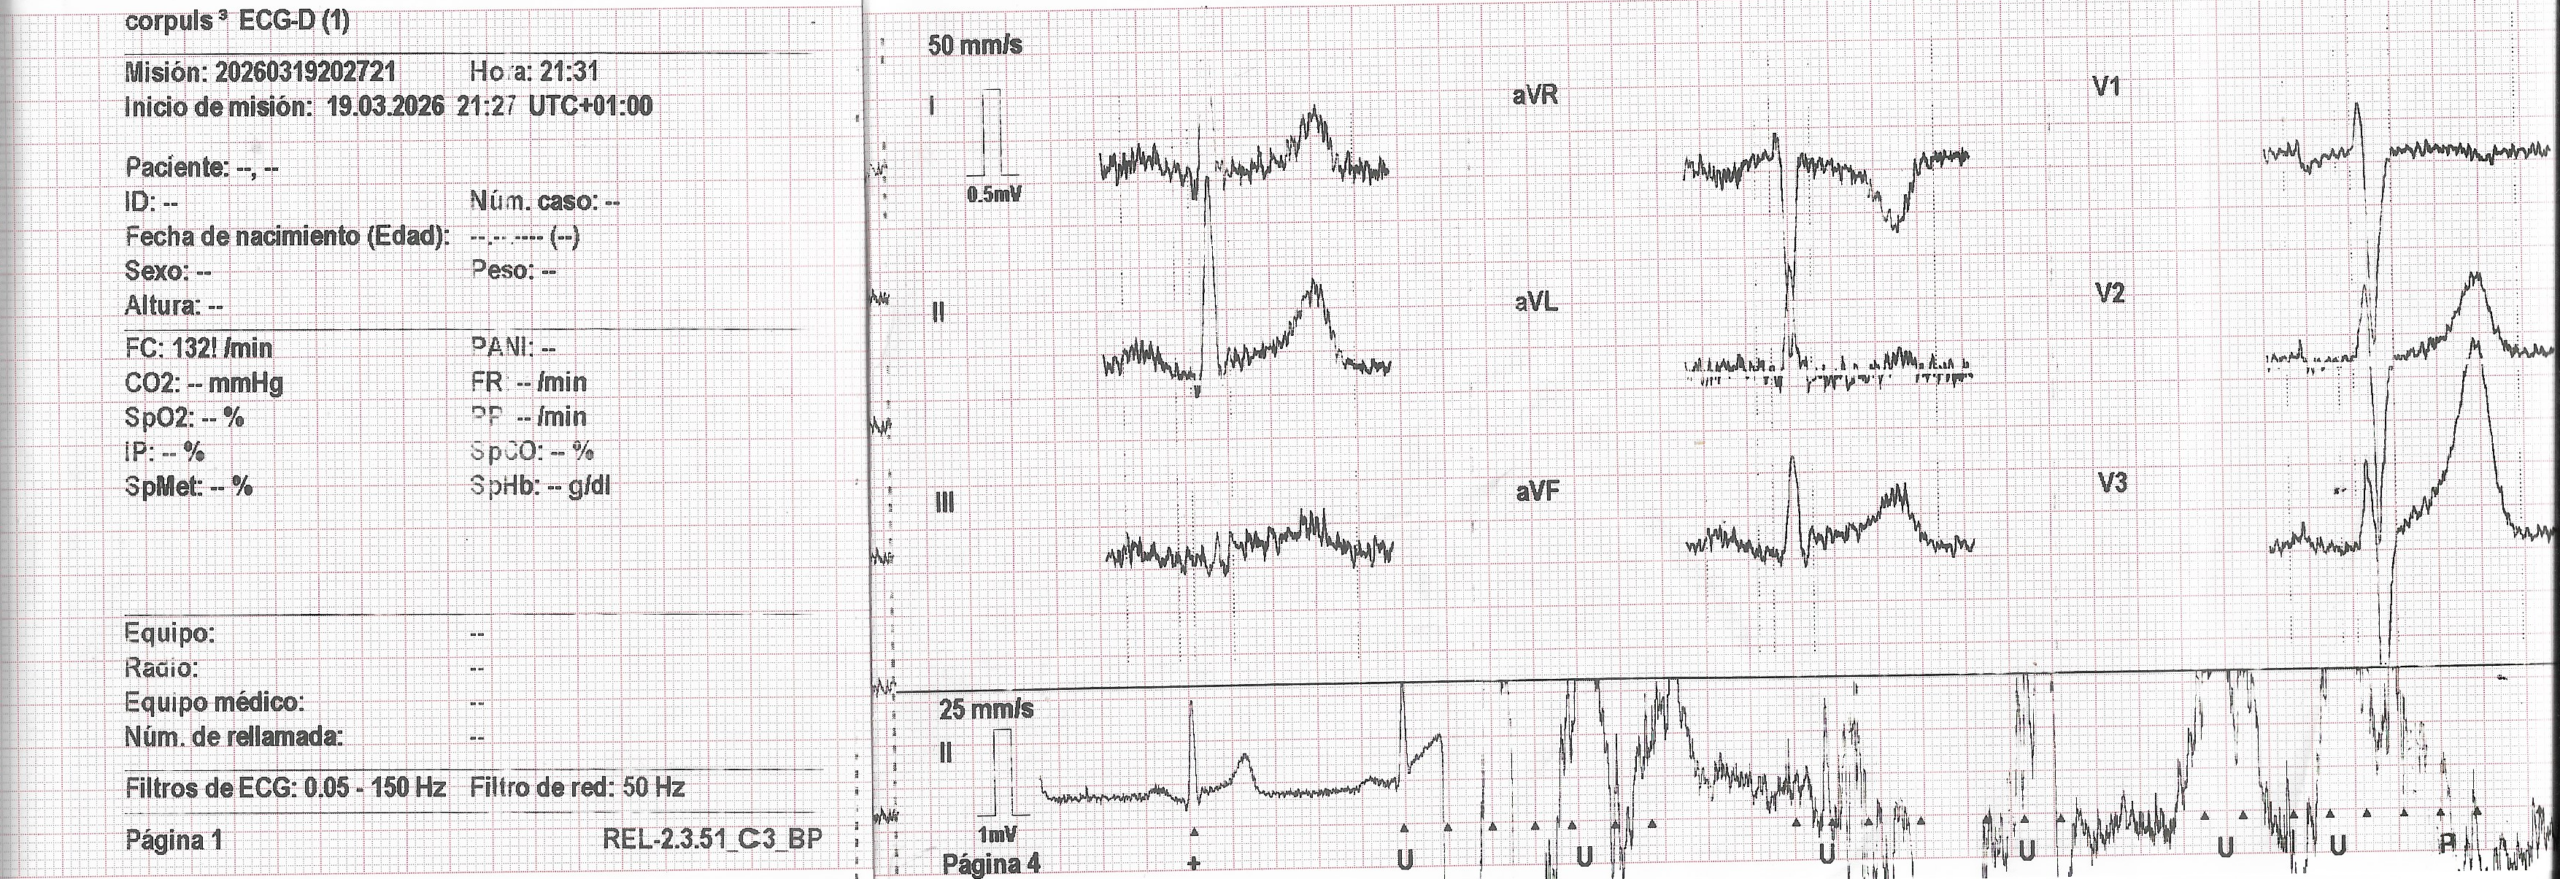

El golpe de suerte se produjo cuando sobre las 21.15, en un momento de lucidez plena, decidí llamar al 112 porque empecé a tener un pequeño dolor en el pecho que no había tenido antes. En menos de 10 minutos, ya tenía en el comedor de casa a mis dos salvadores que tras hacerme un electrocardiograma (ver fotografía) me bajaron a la ambulancia y fue entonces cuando comenzó todo…